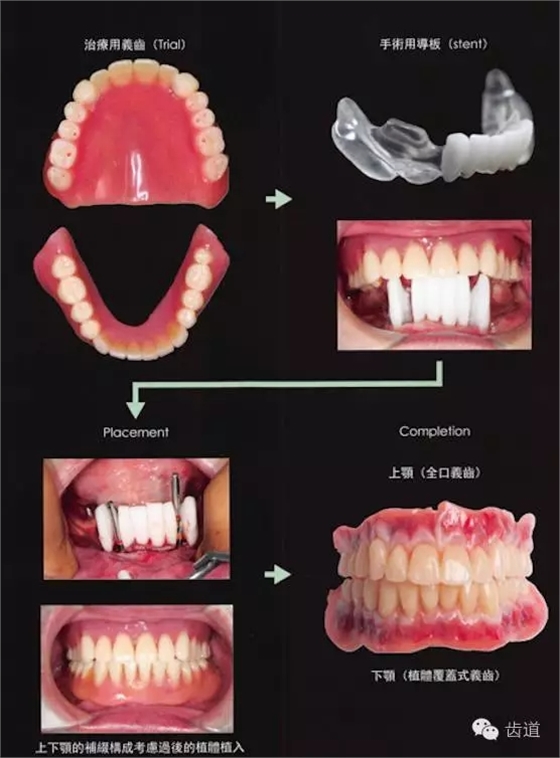

阿部老師告訴我們 為了避免給修復(fù)醫(yī)生制造疑難雜癥,正確的種植修復(fù)步驟是這樣的! 常規(guī)制作上下頜義齒 (天哪!再高大上的種植技術(shù),也解救不了不懂全口義齒的牙醫(yī)) 制作與對(duì)頜關(guān)系正常的手術(shù)導(dǎo)板 植入植體 完成最終修復(fù)!